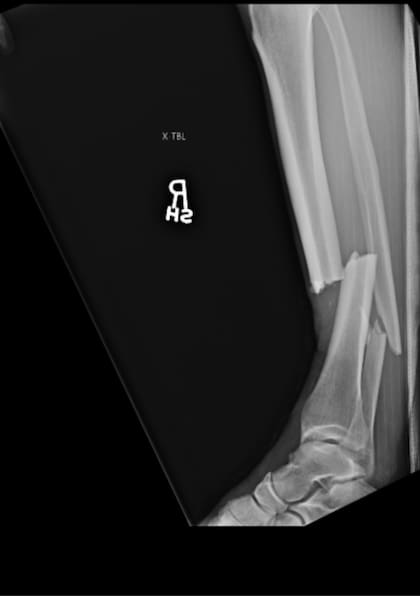

El sábado pasado, Chris Weidman se rompió la pierna en pleno combate contra Uriah Hall. Cuando apenas habían pasado 17 segundos del primer round entre los luchadores de UFC, el neoyorquino de 36 años le lanzó una patada al jamaiquino de su misma edad y terminó tumbado en el piso con una fractura de tibia y peroné. Ahora, el peleador de artes marciales mixtas mostró cómo quedó tras pasar por el quirófano.

“Algunas radiografías antes y después de la operación”, escribió en Twitter, junto a un par de imágenes donde mostraba cómo tenía la pierna apenas fue hospitalizado y cómo le quedó tras la cirugía, donde le colocaron una serie de clavos.

En una entrevista con el medio norteamericano TMZ, Weidman contó que le pusieron una varilla de titanio a través de la tibia y dijo que también se le había roto el peroné. Tal lesión lo obligará a estar entre seis y 12 meses en reposo para poder volver a los entrenamientos.